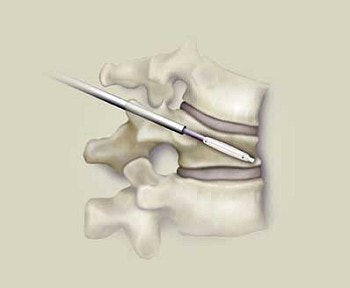

A vertebral compression fracture causing pain and spinal deformity (above). Below, a biopsy needle is guided into the fractured vertebra through a small incision in the skin. Inset shows a magnified view of the interior of the osteoporotic vertebra with the needle in place.